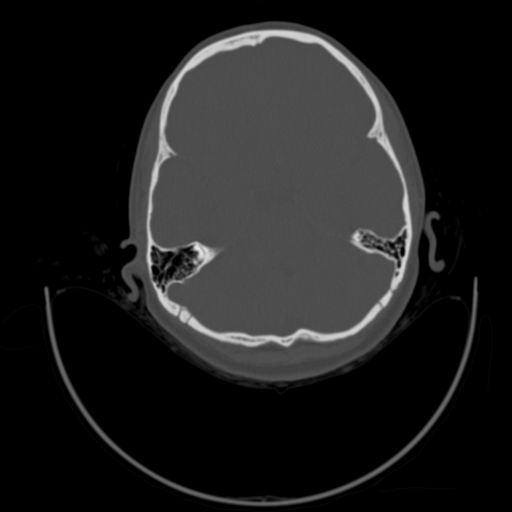

以下是引用随光逐影在2009-3-14 7:58:00的发言:[br]双耳——颞骨ct轴位平扫未见明确异常。